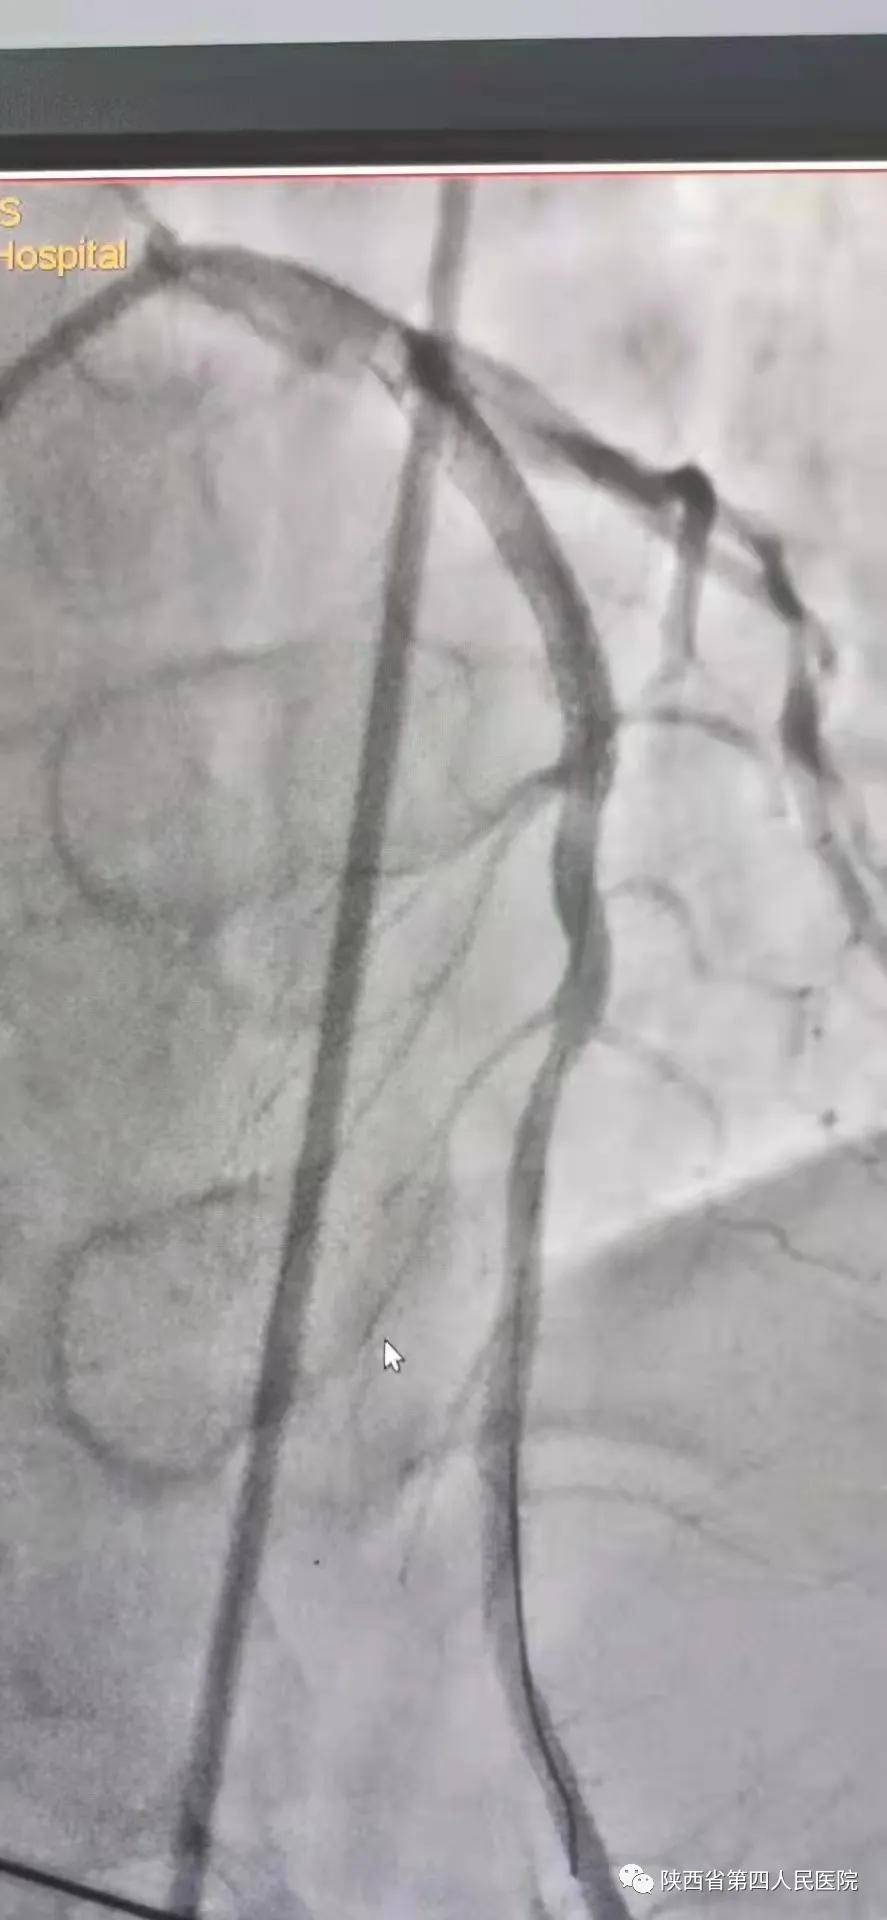

11月10日15时58分左右 , 家住医院附近的中年男性辛先生在家人陪伴下来到陕西省第四人民医院急诊内科门诊诊室 , 满头大汗 , 捂着胸口说胸痛、胸闷、气短 , 急诊科主治医师钟高亮立即安排床位进行留观给予吸氧、心电监护、查体 , 心电图提示:1、窦性心律;2、室性早搏;3、急性下壁、前壁心肌梗死 , 诊断:急性冠脉综合征、心肌梗死 。 随后患者在急诊科留观室病情突然加重 , 意识丧失、四肢抽搐、面色苍白、全身大汗、呼吸急促 , 心电监护提示心室颤动 , 判断其可能为急性心肌梗死心源性休克 , 急诊科和心内科医生立即行胸外心脏按压 , 电除颤三次等对症治疗 , 立即启动胸痛患者抢救应急预案 , 开启绿色通道 , 和患者家属谈话 , 为其迅速办理入院手续 , 给予升压补液扩容等抢救治疗 , 积极完善术前准备 , 联系医务科和介入导管室 , 于16时22分将患者转运至导管室 , 心内科主任、主任医师王选琦和团队副主任医师孙耀林、王崇振 , 主治医师马艳萍共同夺取患者最宝贵生命时间 , 为患者选择了从下肢股动脉穿刺造影 , 从穿刺到开通血管用仅仅只用了十一分钟 。 16时33分顺利完成PAG+PCI支架植入术后成功再通 , 患者转危为安 , 随后入住心血管内科CCU病房继续治疗 。

术后